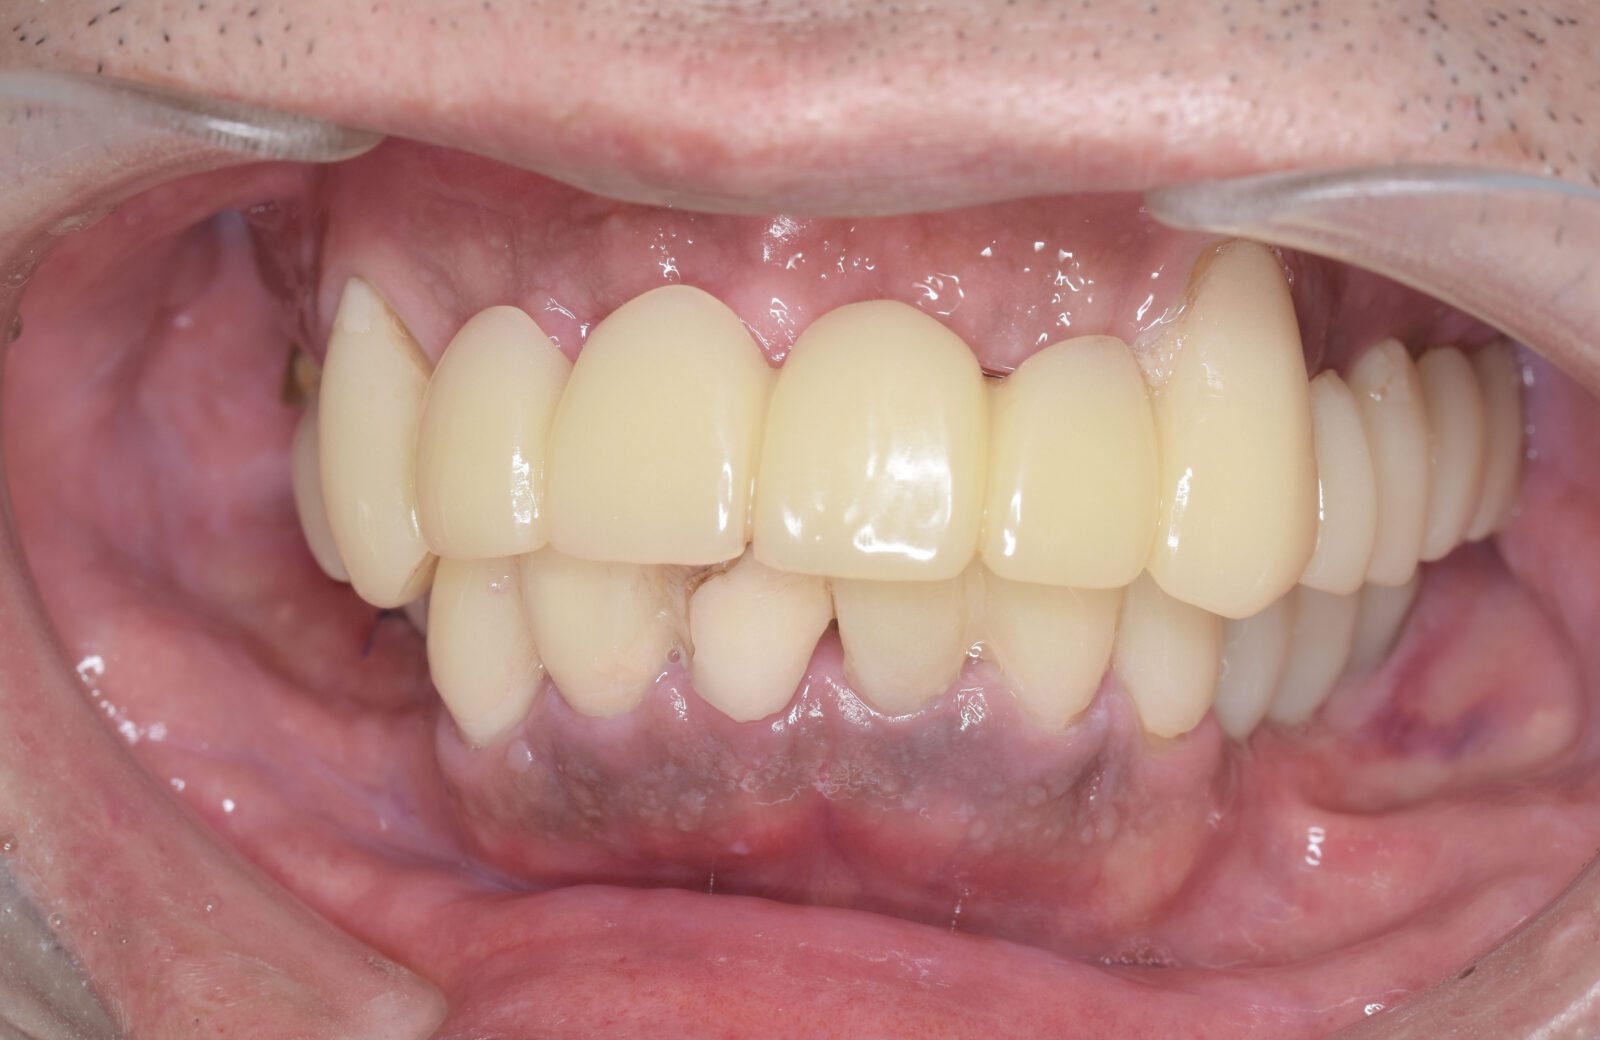

• 治療前

• 治療後

多くの方が、重度のむし歯や歯周病で、抜けてしまっている歯もあるため、まずは虫歯や歯周病治療を行い、残せる歯はしっかり残したうえで、欠損部分の治療を行います。欠損部分に関しては、インプラント、ブリッジ、入れ歯、ケースによってはオールオン4という治療の中から治療法を決定します。